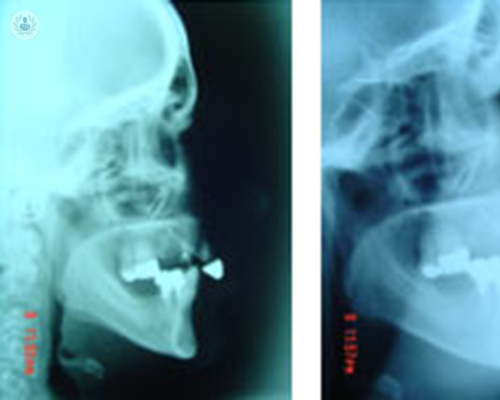

Proceso quirúrgico de la Cirugía Ortognática

Las desarmonías dentofaciales más frecuentes son la mandíbula grande, la mandíbula pequeña, la cara larga, la cara de viejo, la asimetría facial y la mordida abierta. La mejor manera de solucionar estos desequilibrios es mediante la combinación de cirugía ortognática con ortodoncia.